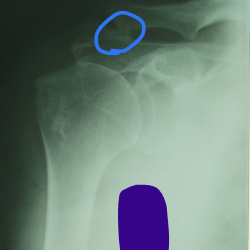

Коллеги, здравствуйте. Мужчина, 60. Анамнез неизвестен. Есть вопросы по плечевому суставу.

1) Красное - нет ли перелома акромиона? Смотрится максимально странно.

2) Желтое - это тендиноз...